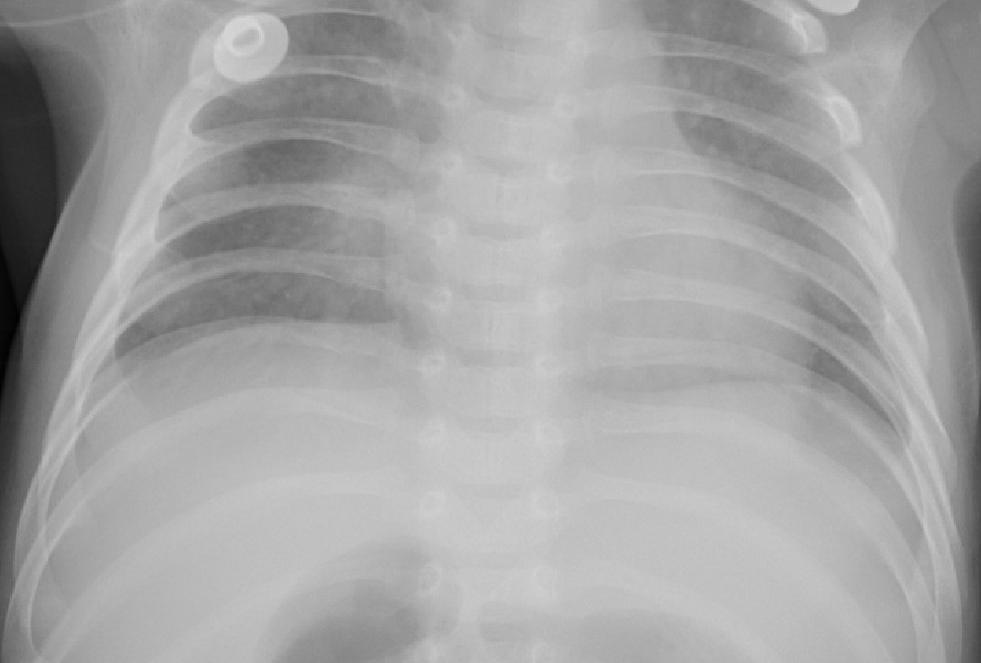

7. Application of RCRI Measure in Image Processing

To ensure the accuracy and reliability of our results, we have taken into account six chest X-ray images from the publicly available chest X-ray 2017 dataset, contributed by kermany2018labeled. These images include samples from healthy individuals and patients diagnosed with pneumonia. For analysis, each X-ray image was converted into a 50×5050\times 50 pixel grid, resulting in 2500 cells per image. The intensity of the gray level of each cell was recorded as a real number ranging from 0 (black) to 1 (white), effectively capturing the grayscale distribution of the image. The α\alpha and β\beta are take as 55.

Using these six images, we generated all 36 possible pairwise combinations. For each pair, we are estimating the Relative Cumulative Residual Information (RCRI), which serves as a measure of discrepancy between the Gray level distributions of the images.

As illustrated in Figure 2, images (a), (b), and (c) correspond to normal chest X-rays, while images (d), (e) and (f) represent pneumonia-infected cases. The calculated RCRI values are presented in Table 10. The matrix reveals distinct clustering patterns that effectively separate the two groups. The top-left 3×33\times 3 submatrix, which includes comparisons among normal images (a, b, c), shows RCRI values ranging from 0.0559 to 0.0637, indicating strong similarity within this group. Similarly, the bottom-right 3×33\times 3 submatrix, corresponding to comparisons among pneumonia-infected images (d, e, f), shows moderately higher but internally consistent RCRI values between 0.1854 and 0.2533, reflecting similarity within this second group. In contrast, RCRI values for comparisons between normal and pneumonia images fall into an intermediate range (approximately 0.0858 to 0.1204), distinctly separating the two classes. These patterns support the application of RCRI as an effective statistical measure for distinguishing grayscale intensity distributions, highlighting its potential in medical image classification and diagnostic support. This consistent difference underscores the effectiveness of the RCRI measure in distinguishing between normal and pneumonia-affected X-rays based on their pixel intensity distributions, supporting its application in medical image analysis for diagnostic purposes.

Refer to caption

(a)

(b)

(c)

(d)

(e)

(f)

Figure 2. Chest X-ray Images

Table 11. Matrix of Relative Cumulative Residual Information (RCRI) for Chest X-ray Image Pairs

a b c d e f

a 0.0512 0.0564 0.0559 0.0858 0.0983 0.0955

b 0.0564 0.0652 0.0637 0.1030 0.1204 0.1156

c 0.0559 0.0637 0.0625 0.0996 0.1159 0.1114

d 0.0858 0.1030 0.0996 0.1854 0.2150 0.1984

e 0.0983 0.1204 0.1159 0.2150 0.2533 0.2334

f 0.0955 0.1156 0.1114 0.1984 0.2334 0.2197